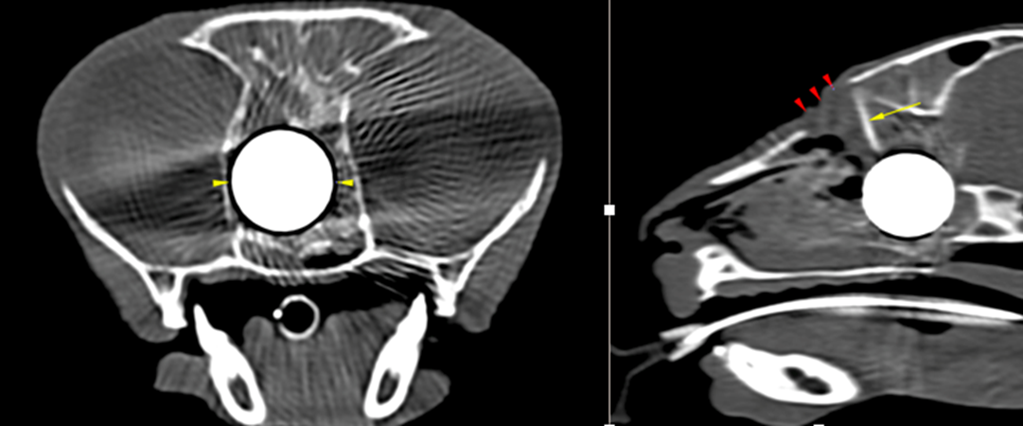

A CT of the skull was performed at Vale Referrals which confirmed the suspicion of a metallic foreign body of the ethmoidal region consistent with a ball-bearing.

The CT also picked up other multiple injuries to the skull and cranium – a large defect within the dorsal maxillary bone consistent with a ballistic entry point, multiple fractures of the skull (bilateral fractures of the medial orbital wall, comminuted fractures of the presphenoidal bone with resultant stenosis of the choanae and rostral nasopharynx)

Perhaps most concerning was that the CT confirmed that the entry of the ball bearing had resulted in fractures the calvarium – the bony casing of the brain and fractures the cribriform plate (a delicate wall of bone in front of the brain) and the ball bearing was sitting millimetres away from the brain itself. Which could have resulted in catastrophic brain injury.